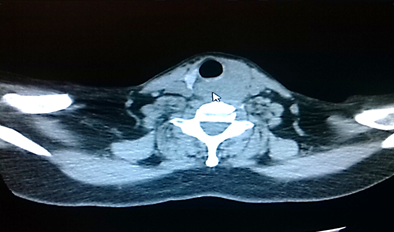

Pruebas de laboratorio: se aprecia leucocitosis en 12.000cel/mm3 y luego progresa a 24.500cel/mm3, polimorfo nuclear 90%, valores de glucosa en sangre elevada. Se le realiza rayos x de cuello (Figura 2. Anexos), y ecosonograma de región cervical, donde se describe una lesión ocupante de espacio alrededor de la tráquea hacia el lado izquierdo, de 4x 2 cm, heterogénea de bordes bien circunscritos. No presenta vascularidad al uso del Doppler. El lóbulo izquierdo del tiroides, muestra efecto de masa en su cara inferior. Concluye con una lesión ocupante de espacio en región traqueal izquierda sugerente de absceso frio. Se le realiza estudio de tomografía computarizada de cuello (Figura. 3, 4, 5. Anexos), y tórax, apreciando en región lateral izquierda del cuello, hiperdensidad paralela a la tráquea y glándula tiroidea, haciendo efecto de masa compresiva sobre las estructuras cercanas.

Figura 3. Tomografía axial computarizada de región cervical. apreciando en región lateral izquierda del cuello, hiperdensidad paralela a la tráquea y glándula tiroidea, haciendo efecto de masa compresiva sobre las estructuras cercanas.

Fuente: Fotografía realizada por Dra. María Pulgar.